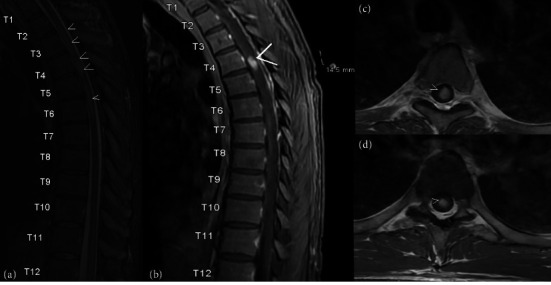

组织胞浆菌病是一种由真菌荚膜组织胞浆菌引起的真菌感染,很少出现中枢神经系统(CNS)表现,包括脑膜炎、脑炎、局灶性脑或脊髓病变以及中风综合征。由于患者之间的差异,中枢神经系统组织浆菌病是一种难以进行临床诊断的疾病,而没有高灵敏度的诊断测试则进一步阻碍了诊断。在这里,我们提出一个独特的案例,46岁的男性免疫功能低下,由于1型糖尿病和弥散性组织胞浆菌病作为脊髓病的急性表现。患者在就诊前几天左腿无力,神经学检查显示有急性胸椎脊髓病的迹象,特别是与布朗-萨默综合征有关。核磁共振成像显示胸脊髓强化病灶,同时伴有多发脑强化病灶,双侧肾上腺肿块和无数肺结节。活检结果显示酵母形式与组织浆菌种类一致。

Histoplasmosis is a fungal infection caused by the fungus Histoplasma capsulatum that can rarely present with central nervous system (CNS) manifestations that include meningitis, encephalitis, focal brain or spinal cord lesions, and stroke syndromes. Because of this variation from patient to patient, CNS histoplasmosis is a difficult clinical diagnosis to make, which can be further hindered by no highly sensitive diagnostic testing available. Here, we present a unique case of a 46-year-old male immunocompromised due to type 1 diabetes mellitus with disseminated histoplasmosis as an acute presentation of myelopathy. Patient had left leg weakness for a few days prior to presentation and a neurological exam remarkable for signs of acute thoracic myelopathy, specifically concerning for Brown-Séquard syndrome. MRI imaging demonstrated an enhancing thoracic spinal cord lesion along with multiple cerebral enhancing lesions, bilateral adrenal masses, and innumerable pulmonary nodules. Biopsy results demonstrated yeast forms consistent with Histoplasma species.